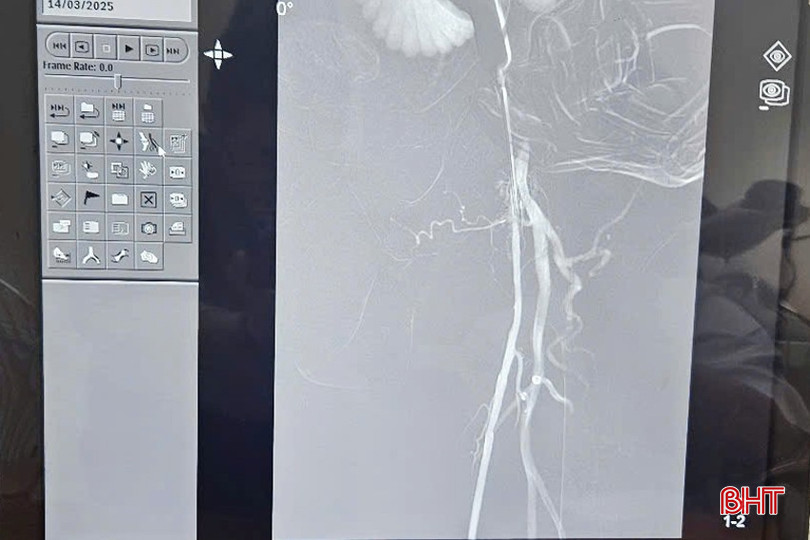

Hình ảnh mạch chi của bệnh nhân qua chụp số hoá xoá nền.

Việc chuyển giao được thực hiện trên bệnh nhân Đ.Q.V (84 tuổi, huyện Thạch Hà) bị xơ vữa động mạch chi dưới trên nền bệnh đái tháo đường không phụ thuộc insulin. Sau khi thăm khám, đánh giá tổng thể tình trạng của người bệnh, các chuyên gia Bệnh viện Trung ương Quân đội 108 phối hợp với các bác sỹ Khoa Tim mạch tiến hành chụp số hoá xoá nền động mạch chi dưới và nong, đặt khung giá đỡ mạch chi. Sau can thiệp, tình trạng bệnh nhân ổn định, tình trạng xơ vữa động mạch được xử lý.